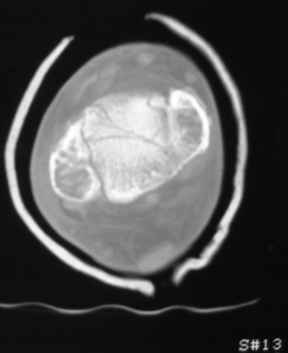

Остеопороз (продолжение 3) - данные КТ

Юрий Алексеевич Булахтин 07 Ноябрь 2009, 16:27

|

Уважаемые коллеги!

Продолжая тему представляю данные КТ нашей пациентки.

Вопросы к сообществу - в сообщении №2.

Юрий Алексеевич Булахтин